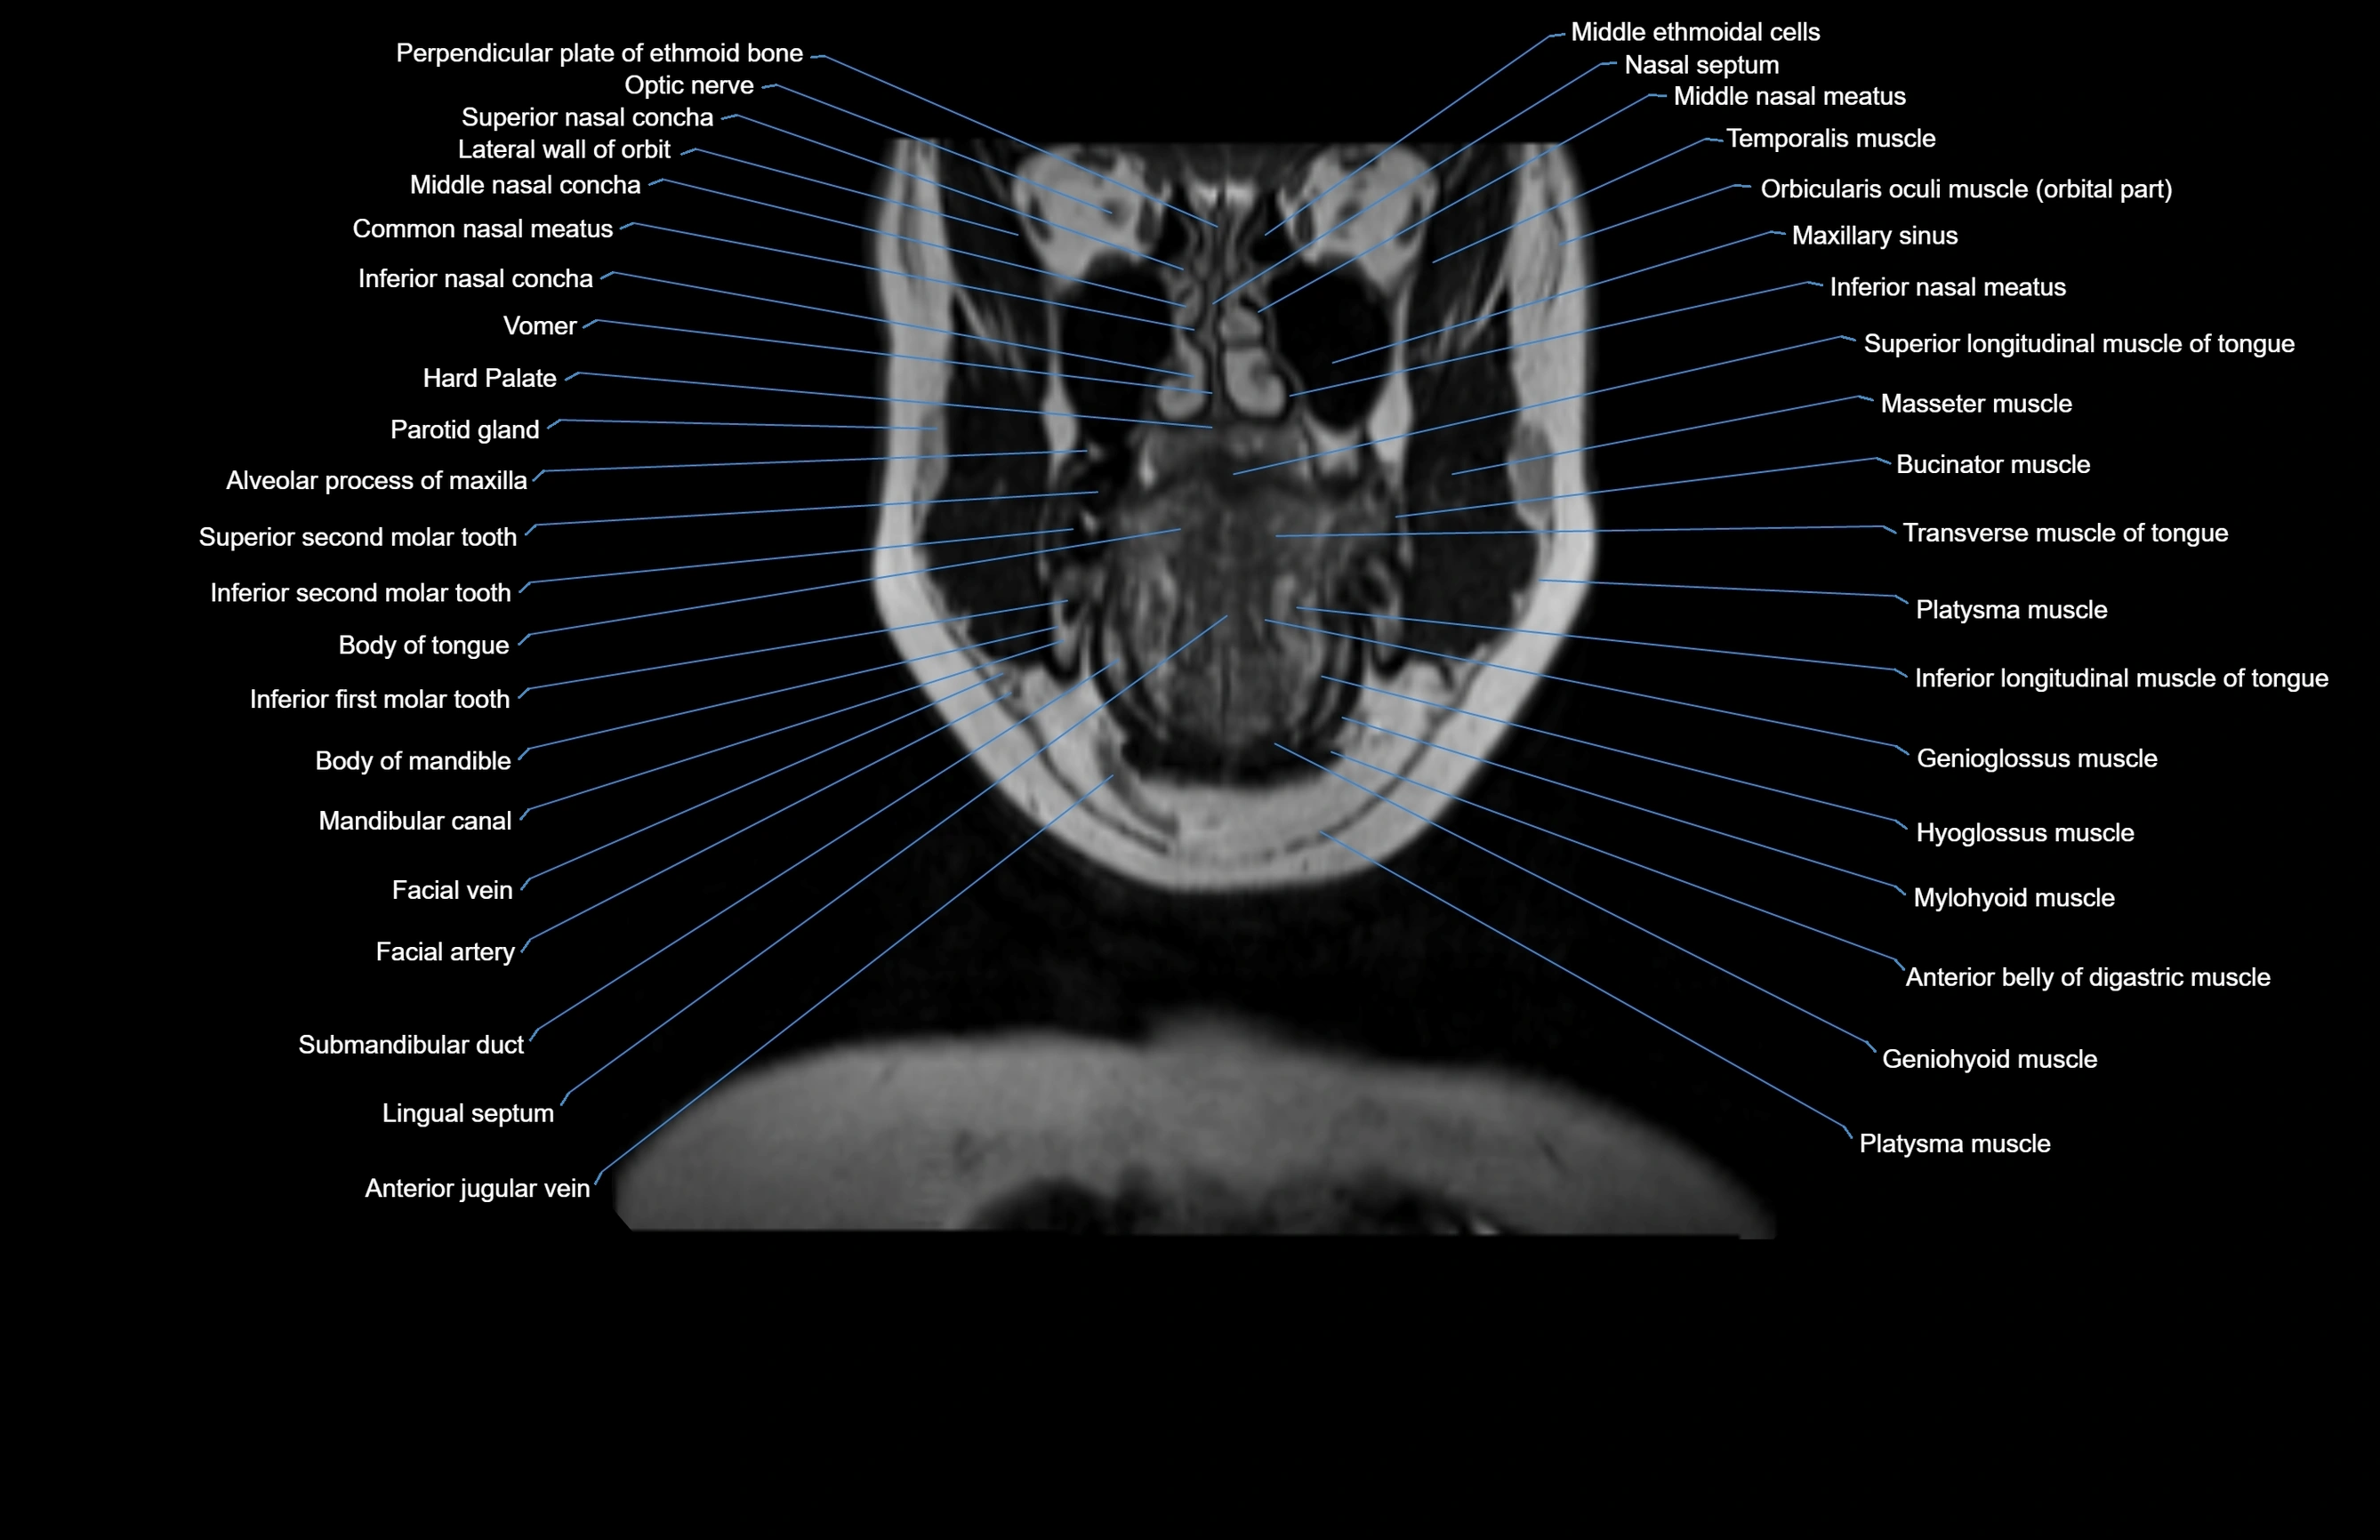

MRI images